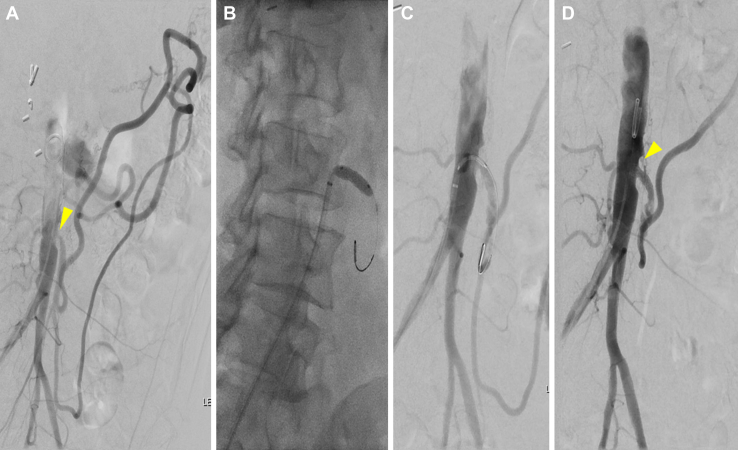

Fig 4.

A, Preoperative flush aortogram of patient 4 showing severe stenosis (arrowhead) in the inferior mesenteric artery (IMA), with the IMA feeding a robust collateral network to the viscera and lower extremities. B, Balloon angioplasty showing residual waist. C, Stent placement with improved stenosis (arrowhead) and flow to the meandering mesenteric artery.

Patient 4

A 57-year-old female patient had presented with a 6-month history of postprandial abdominal pain, a 25-lb weight loss, and food fear. CTA revealed long-segment celiac artery and SMA occlusions with ostial IMA stenosis. Because of a nearly orthogonal takeoff of the IMA, the patient was brought electively for mesenteric angiography via a common femoral approach, which demonstrated robust retrograde filling of the SMA via a large meandering mesenteric artery. The IMA was selected and underwent angioplasty and stenting with a bare metal stent (Fig 4). However, on POD 1, the patient had developed severe abdominal pain and vomiting after a PO diet challenge. She underwent urgent aortoceliac and aorto-SMA bypass with a bifurcated graft. The IMA was found to be patent, with a water hammer pulse distal to the stent. Therefore, dissection of the meandering mesenteric artery was suspected. The patient’s postoperative course was unremarkable, and the patient was discharged on POD 7 after surveillance CTA had demonstrated patent aortic–visceral bypasses but with occlusion of the IMA stent. The patient had not had a return of mesenteric ischemia symptoms through 18 months of follow-up.